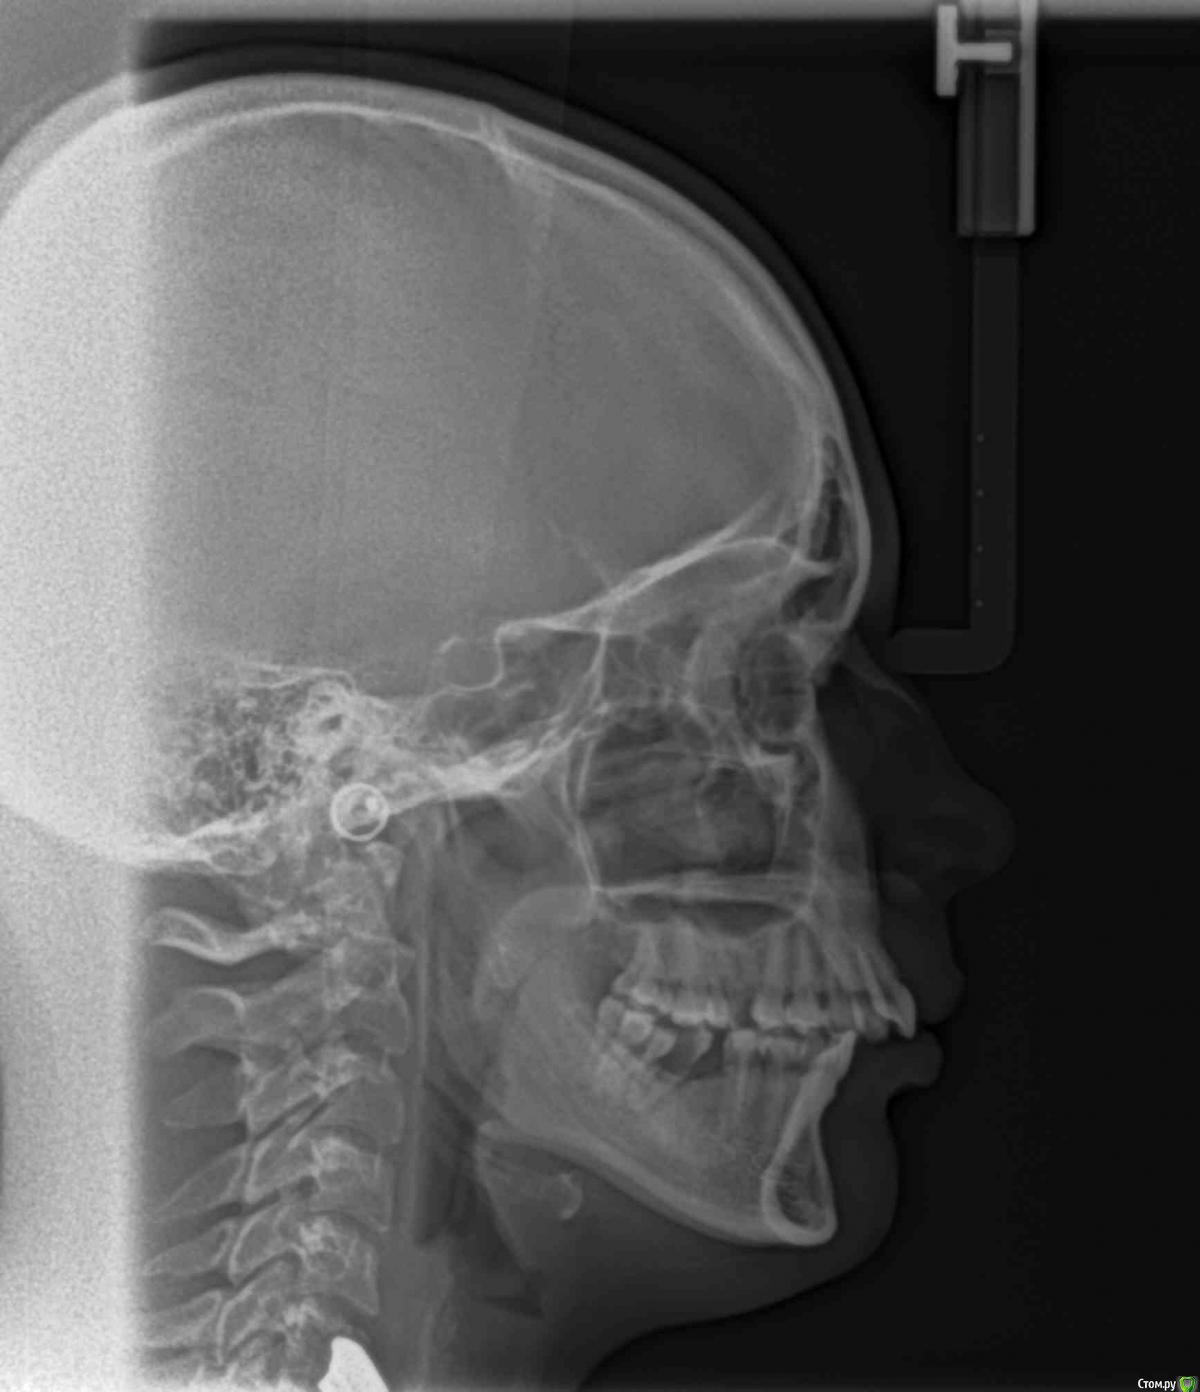

Здраствуйте.меня зовут Ольга.мне 26 лет.брекеты ношу 2 г и 7 м.Подскажите мне пожалуйста что можно сделать в моей ситуации.У меня дистальный прикус.был 11 мм.Не было одного шестого зуба на в.ч с одной стороны.и под удаление был уже второй.поэтому врач перетенул 5,4 и все остальные зубы на место 6.сагитальная щель осталась 5 мм.но врач сказал что сделать ничего со мной нельзя тут только операция...чего я очень сильно боюсь.и предложила сделать наклон нижних передних зубов чтоб хоть как то было смыкание...Стабилен ли будет такой вариант или что можно сделать?!пожалуйста подскажите.Снимки и фото прилогаю.снимки сделаны перед брекет системой.почему то последние фото загрузились перевёрнутыми

НЕТ. наклонять нижние резцы до смыкания  при щели в 5 мм нельзя !

в идеале - выравнивание окклюзионной плоскости (у Вас  боковой отдел на взлет идет)  и постановка нижней челюсти в правильное положение (либо аппараты по типу Гербста либо операция - решается при расчете снимков, либо оставлять как есть)